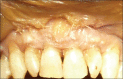

The containment of the elevator muscle of the upper lip and wing of nose was used for the treatment of patients with gummy smile. This technique had corrected esthetic alterations of smile, reducing the upper lip elevation, which results in a smaller gingival display. An upper lip lengthening as well as a reduction in the upper lip shortening when the patient smiled could be observed. The high smile line was corrected without compromising the labial harmony. This study presents an innovative and effective therapeutic option to obtain a natural and harmonious smile. The patient expressed a high degree of satisfaction.